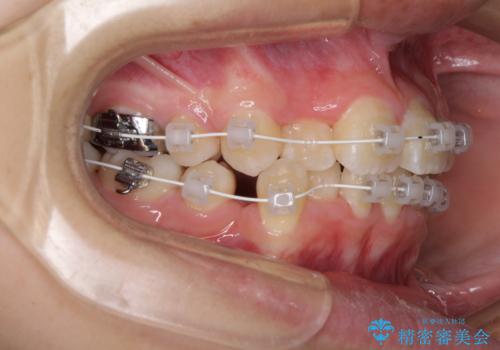

- 上下の八重歯と前歯のデコボコを気にして来院された患者様です。

右上の八重歯が特に著しく、上顎正中が右側にシフトしていました。

デコボコが強いため小臼歯4本を抜歯し、上顎正中を左側に移動させるために補助装置を使用して、ワイヤー装置にて矯正治療を行うこととしました。